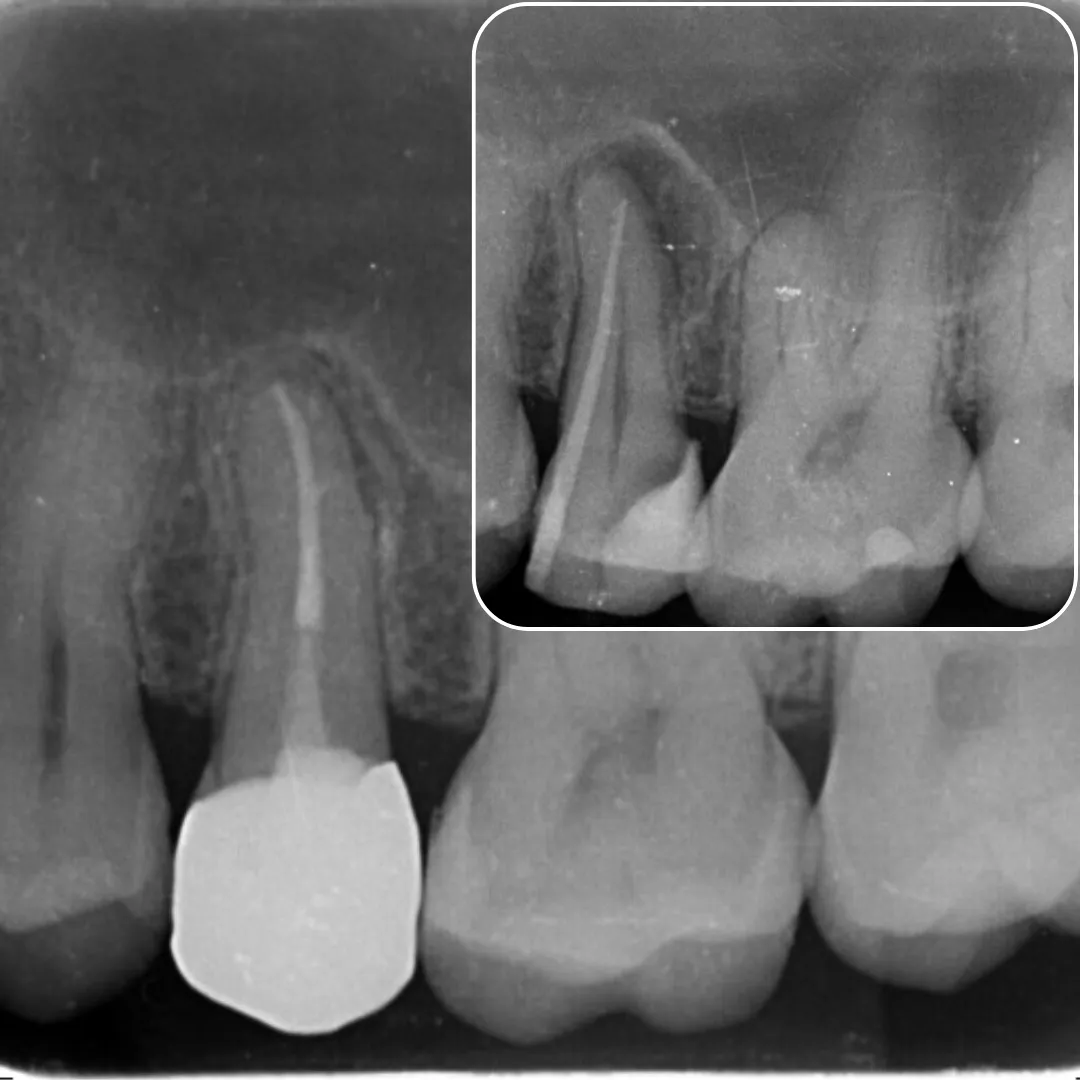

• Management of curved canals, calcified canals, and difficult access cases.

• Re-treatment cases of non-healing or failed root canals.

• Advanced use of CBCT and magnification (microscope) for navigation.